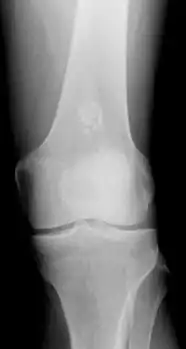

Diagnosistic tests include medical imaging.[2] Appearances on X-ray show a small lobe-shaped, dark tumor in the middle of the bone.[2] It typically contains white spots; calcified chondroid matrix (a "rings and arcs" pattern of calcification).[2] It does not extend into soft tissues.[6] Magnetic resonance imaging (MRI) and CT scan may be requested to further evaluate the tumor.[8]

Differentiating an enchondroma from a bone infarct on plain film may be difficult. Generally, an enchondroma commonly causes endosteal scalloping while an infarct will not. An infarct usually has a well-defined, sclerotic serpentine border, while an enchondroma will not. When differentiating an enchondroma from a chondrosarcoma, the radiographic image may be equivocal; however, periostitis is not usually seen with an uncomplicated enchondroma.